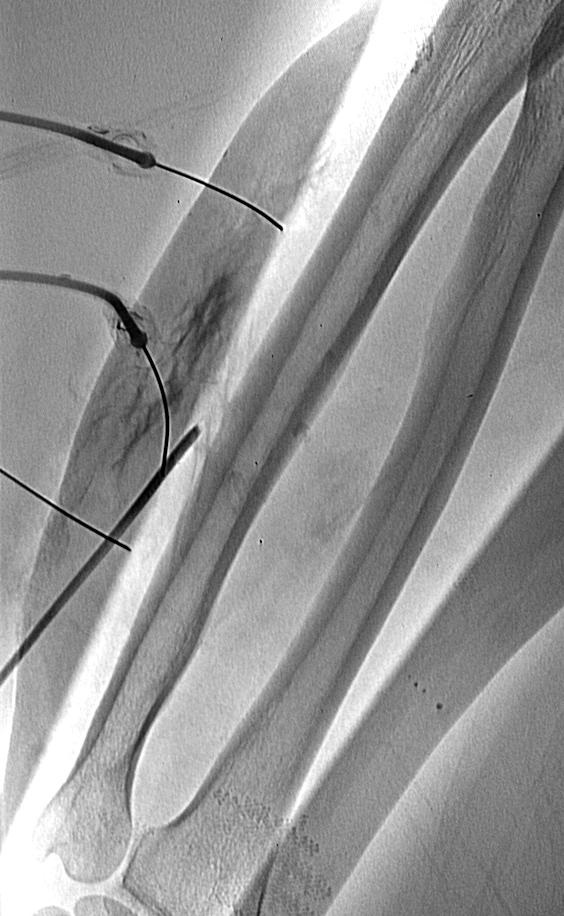

控制静脉血流措施包括

-

整形外科使用的止血带(Orthopaedic tourniquet)

阻塞球囊(Occlusion balloon catheter)

- 阻塞静脉 Venous

- 阻塞动脉 Arterial

从明显的静脉囊栓塞其它较小的流出道静脉,如果存在的话(Embolization of other smaller outflow veins from dominant venous sac if present)

- 弹簧栓子Coils, 血管塞plugs, 胶glue, 液体栓塞剂liquid sclerosants

球囊导管 Control venous outflow

Control venous outflow

目标是获取静脉内造影剂滞留(Aim should be to obtain contrast medium stasis within central venous component)

可以安全地应用液体硬化剂(Allows safe use of liquid sclerosant agents)

使这些栓塞剂对血管壁有较好的影响(Better effect of these agents on vessel wall)

球囊控制

弹簧栓子控制静脉流出道